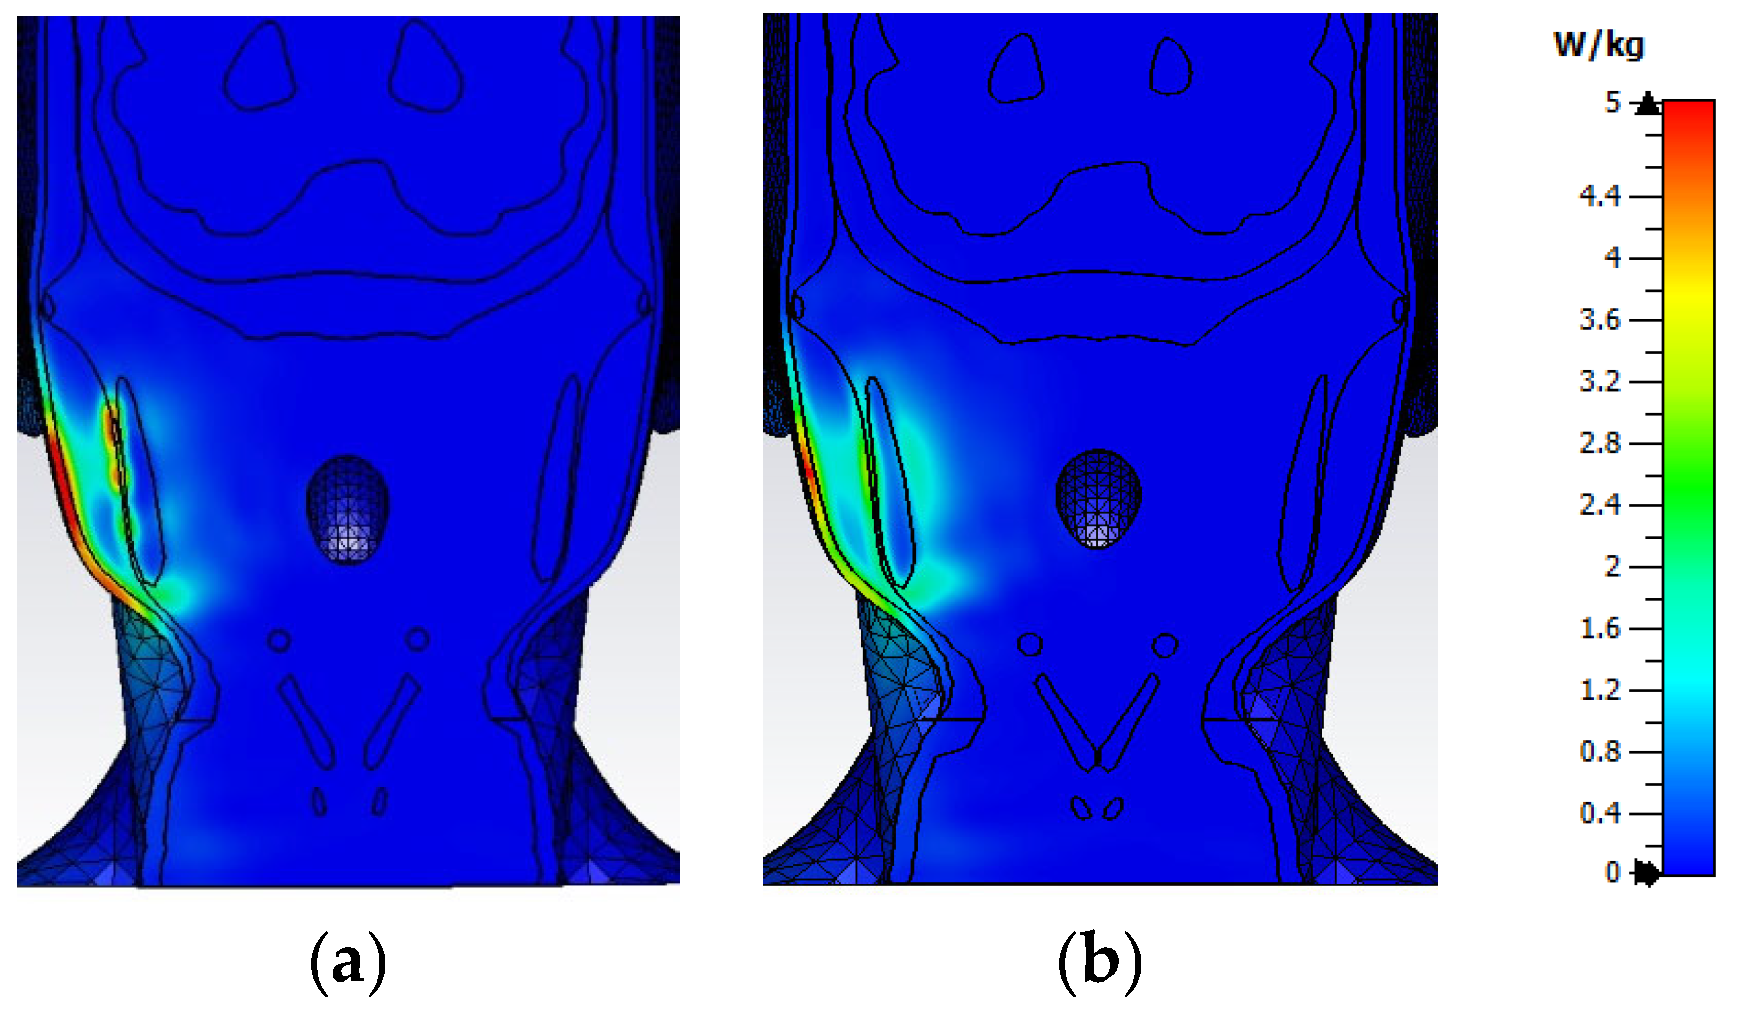

3.2. Distribution of SAR Values Within the Model of the Head of a User

3.3. Impact of the Face-to-Phone Distances on the Electric Field and SAR Distribution in the Implant Vicinity